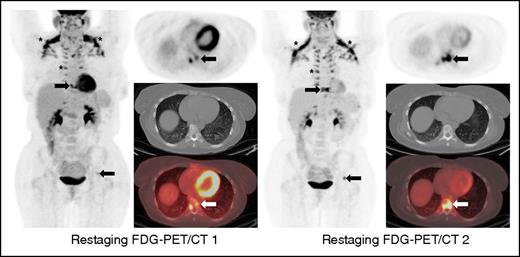

This case illustrates a discrepancy between the revised Lugano Classification (PD) and the immune-related response criteria (PR) given the fact that the immune-related response criteria do not take into consideration PET/CT findings. This type of discrepancy is particularly notable in cases with bone marrow involvement. Oftentimes, lymphomatous involvement of the bone marrow is either not measurable (due to absence of soft tissue component) or imperceptible on CT. Therefore, these findings cannot be integrated in the tumor burden of the immune-related response criteria. Restaging PET-CT is at 12 weeks. Restaging PET/CT 2 at 20 weeks demonstrates new areas of FDG uptake in the left side of T9 vertebral body (arrows) and increasing uptake in the left acetabulum, suggesting increasing extent of marrow disease, whereas this is barely seen on CT. Marked physiologic uptake is also seen in brown fat (asterisks).